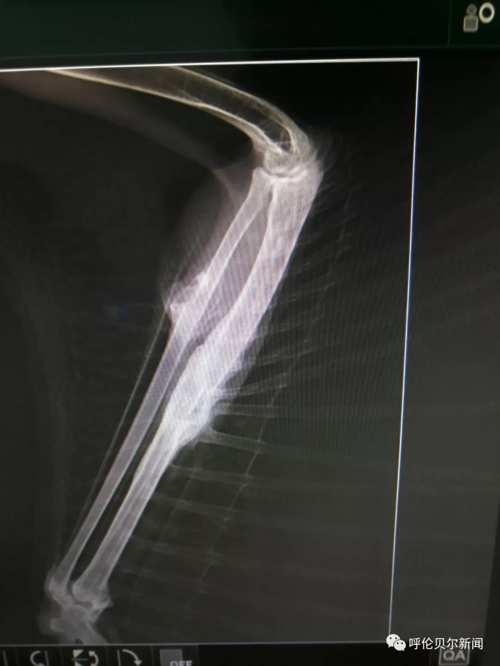

“我折了,希望有好心人能救助我!”2018年8月25日中午13:54分,双龙发了第一条关于这只雕鸮的微信朋友圈。“医院给雕鸮拍了x光片,发现右尺骨和桡骨两处骨折。身边没有能给宠物做手术的医生,我把图片发到朋友圈求助,咨询我市多名专家,他们都说桡骨非常细而且骨头很脆很难固定,手术难度太大。”双龙说。 “伤口感染,羽毛上的血渍结成了块,鸟的眼神里满是警惕和无奈,草原猛禽的风姿不再,可怜巴巴的样子,很让人心疼。”一直跟踪采访的新右旗融媒体中心记者巴图毕力格说。 >>>2018年8月31日 一边精心喂养,一边筹集为雕鸮治疗的资金,并通过微信群等方式寻找医生。经一名台湾野生保护志愿者联系,8月31日,双龙联系了毕业 于中国农业大学动物医学院、中国执业兽医师张拥军医生。 “我是一只国家二级保护动物雕鸮,我受了很重的伤,幸运的是我遇到双龙老师和张医生,他们没有放弃我……”一段雕鸮自述在腾讯公益被转载,很多野生动物保护志愿者解囊相助。5232.46元的爱心款向巴尔虎草原汇集。

在北京的张拥军医生看了X光片后表示可以进行手术,但是现在跨省运输国家二级野生保护动物审批手续繁琐时间太长,为了能够尽快手术,张拥军医生决定在海拉尔“出诊”。几经周折,双龙在海拉尔找到具备做手术条件的玩皮宠物医院,这家医院不仅同意免费提供手术场还表示愿意提供各种手术器具和药品。

>>>2018年9月3日 9月的草原日渐苍凉。清晨,双龙带着雕鸮行程300多公里来到海拉尔。一场秋雨让海拉尔这座城市清新怡人。玩皮宠物医院手术室内,来自北京的张拥军医生为雕鸮做了手术,海区几家宠物医院的医师均前来做助理、观摩学习。“手术难度比较大,术后休养也很重要,我会尽全力完成的。”张拥军医生结合20多年的临床经验,为在场的技术人员讲解手术要领。手术期间,记者进入手术室,看到双龙一边给张医生做助手,一边用蒙语安抚雕鸮。

经过近3个多小时的紧张繁忙,手术顺利完成。 经过一夜的观察,雕鸮各项体征趋于正常,9月4日上午,双龙带着雕鸮返回新右旗精心喂养。 >>>2018年9月14日 “拆线第二天,雕鸮状态良好,食量大增,每天能吃1斤肉,快养不起你啦!”双龙的朋友圈总会发一些动态,让关心雕鸮的人了解它况。